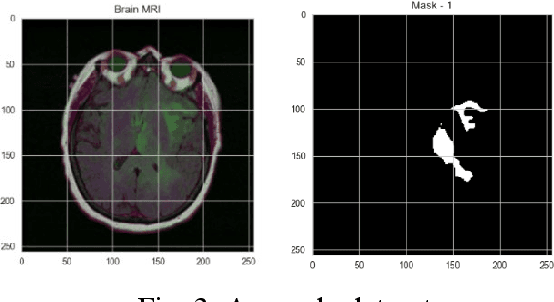

Abstract:Accurate identification and localisation of brain tumours from medical images remain challenging due to tumour variability and structural complexity. Convolutional Neural Networks (CNNs), particularly ResNet and Unet, have made significant progress in medical image processing, offering robust capabilities for image segmentation. However, limited research has explored their integration with human-computer interaction (HCI) to enhance usability, interpretability, and clinical applicability. This paper introduces ResUnet++, an advanced hybrid model combining ResNet and Unet++, designed to improve tumour detection and localisation while fostering seamless interaction between clinicians and medical imaging systems. ResUnet++ integrates residual blocks in both the downsampling and upsampling phases, ensuring critical image features are preserved. By incorporating HCI principles, the model provides intuitive, real-time feedback, enabling clinicians to visualise and interact with tumour localisation results effectively. This fosters informed decision-making and supports workflow efficiency in clinical settings. We evaluated ResUnet++ on the LGG Segmentation Dataset, achieving a Jaccard Loss of 98.17%. The results demonstrate its strong segmentation performance and potential for real-world applications. By bridging advanced medical imaging techniques with HCI, ResUnet++ offers a foundation for developing interactive diagnostic tools, improving clinician trust, decision accuracy, and patient outcomes, and advancing the integration of AI in healthcare workflows.